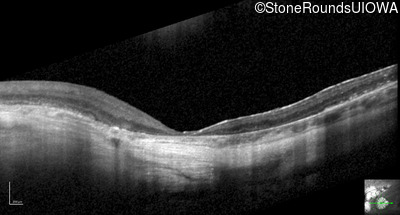

Optical Coherence Tomography - Right - 20/125 +1

Exemplar / OCT Stack

OCT Stack